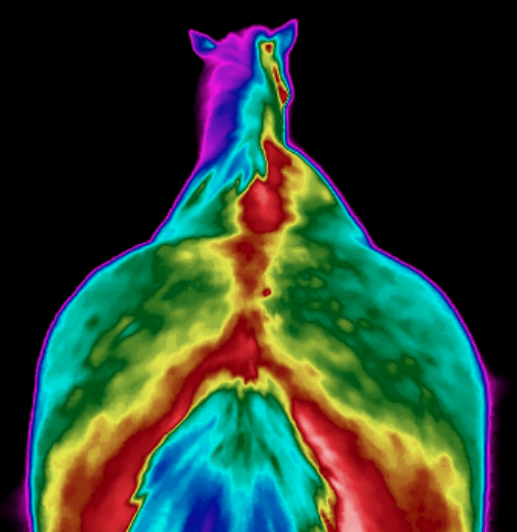

Bilder aus der Praxis:

Thermografie eines Pferderückens

Thermografie eines Pferderückens

Thermografie eines Pferderückens von hinten